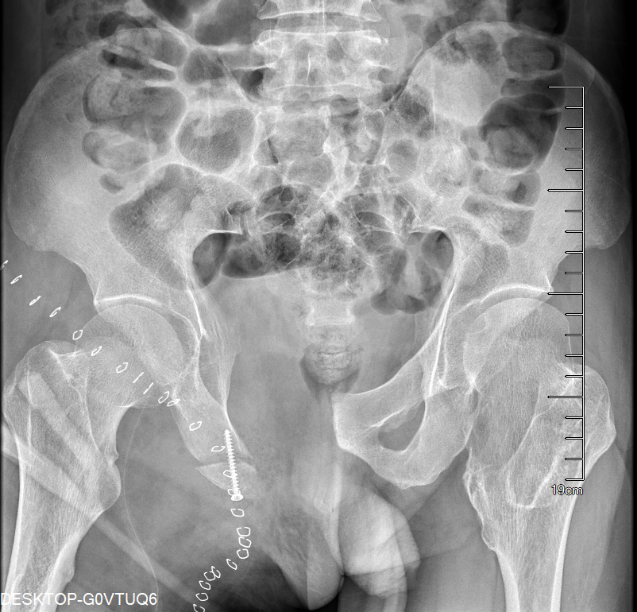

我院骨科王伟东副主任接诊后详细询问了患者疾病发展过程,并为患者做了全身体格检查,仔细查阅了患者的检查报告,综合各方面信息后,诊断患者患有“先天性多发骨软骨瘤病”,并且右耻骨上支的骨软骨瘤已经恶变为继发性软骨肉瘤。目前患者远处脏器尚未出现转移,右耻骨病灶周围解剖屏障尚完整,王主任建议患者手术治疗。

图片 2.png图片 3.png

术前CT